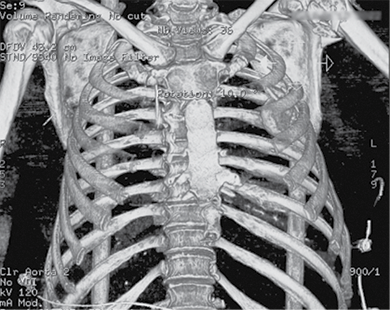

A 58-year-old patient was admitted to the Emergency Department of level I Trauma Center in August 2022 due to polytrauma sustained in a car accident. On arrival, the patient’s condition was severe, with decreased consciousness (GCS score of 12), unstable hemodynamic, subcompensated peripheral circulation, blood pressure of 62/32, and heart rate of 78 beats per minute. There was reduced breathing on the left side with a respiratory rate of 18 breaths per minute and an oxygen saturation (SpO2) of 85.0%. Palpation revealed pain in the left posterior chest. X-rays and CT scans were performed, which revealed a traumatic hemothorax on the left side, humeral head within the pleural cavity, three rib fractures, lung contusion, and hematoma.

Figure 1. First X-ray and computer tomography upon admission (with humeral head shown)

Figure 2. Subsequent 3D reconstruction